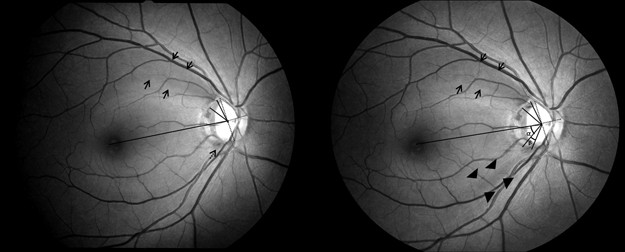

칼라 안저 소견(color fundus photo)에서 발견되거나,

적색차단필터 안저 사진(red free fundus photo)에서 발견되거나,

RNFL defect가 있으면 해당부위가 어둡고 검게 보이기 때문에,

이를 쉽게 발견하기위해서는 기본적으로 안저에 RPE의 색소침착이 많을수록 관찰이 쉽습니다.

시신경유두의 상이측이나 하이측의 경우,

RNFL섬유가 활모양으로 휘어서 시신경유두로 들어오기 때문에,

RNFL defect가 발생하게되면, 칼라 혹은 적색차단필터(RNFL 관찰전용) 안저사진에서 쐐기모양의 어두운 모양이(wedge shape)이 발견됩니다.